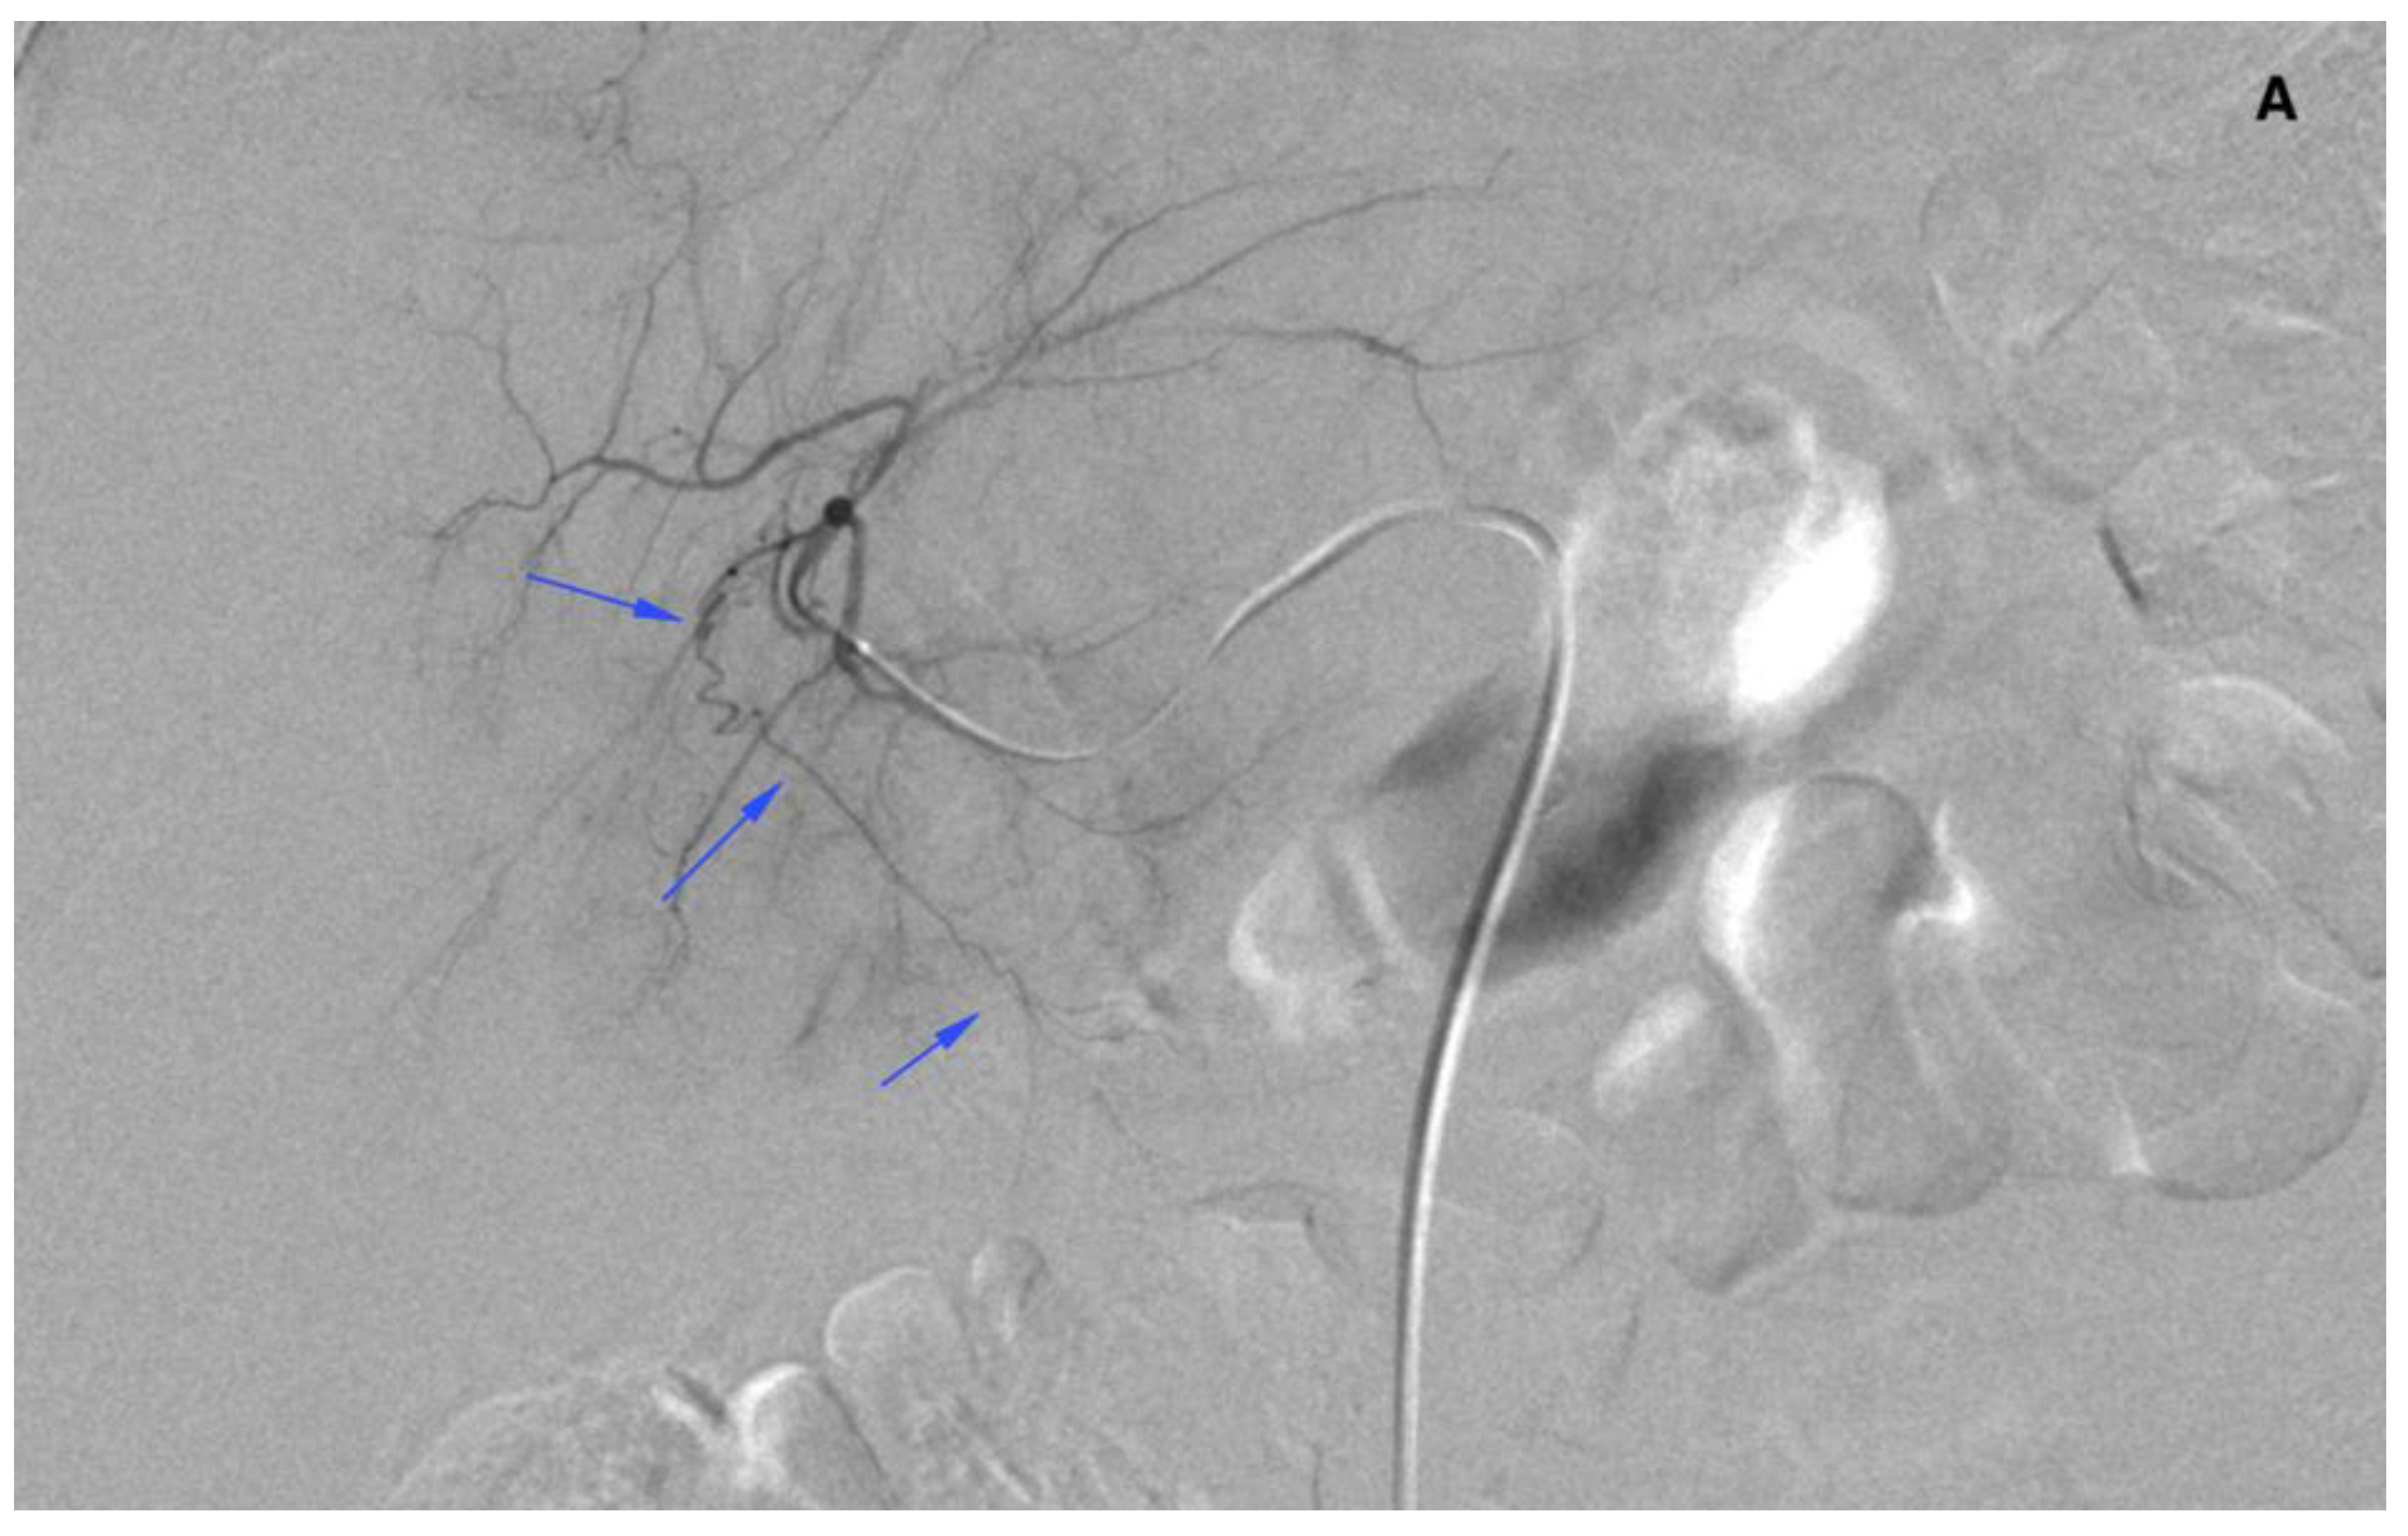

The Osirix (Pixmeo SARL, Geneva, Switzerland) software was used to carry out measurements on DSA (digital subtraction angiography) images (Figure 1). Three-month follow-up was used to observe potential early adverse events linked with extrahepatic radiated microspheres spread, (i.e., cholecystitis, gastric ulcer, or skin radiation). It consisted of a patient’s physical examination, liver function tests, and complete blood count assessments at 1–5 days and every 2–3 weeks as well as a follow-up CT (computed tomography) two to three months after the SIRT procedure. The presence of adverse events linked with extrahepatic arteries embolization in the work-up procedure was assessed with Common Terminology Criteria for Adverse Events (CTCAE v 3.0).

Figure 1.

A general scheme presenting the measurement procedure. Thin arrows indicate origins of the cystic artery (CA) and the right gastric artery (RGA). Numbers at thick arrows (1–4) indicate distances (lines) of the tip of the microcatheter from the cystic artery, the gastroduodenal artery (for right lobe injection), the gastroduodenal artery (for left lobe injection), and the right gastric artery, consecutively.